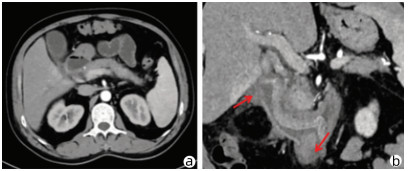

Lymphoepithelioma-like hepatocellular carcinoma: A case report

Xiaotong QIU, Zhengqi WU, Xuxiang XIA, Guoyue LYU

2022, 38(3): 634-635. DOI: 10.3969/j.issn.1001-5256.2022.03.027

Abstract(762) HTML (934) PDF (2924KB)(68)

Abstract: